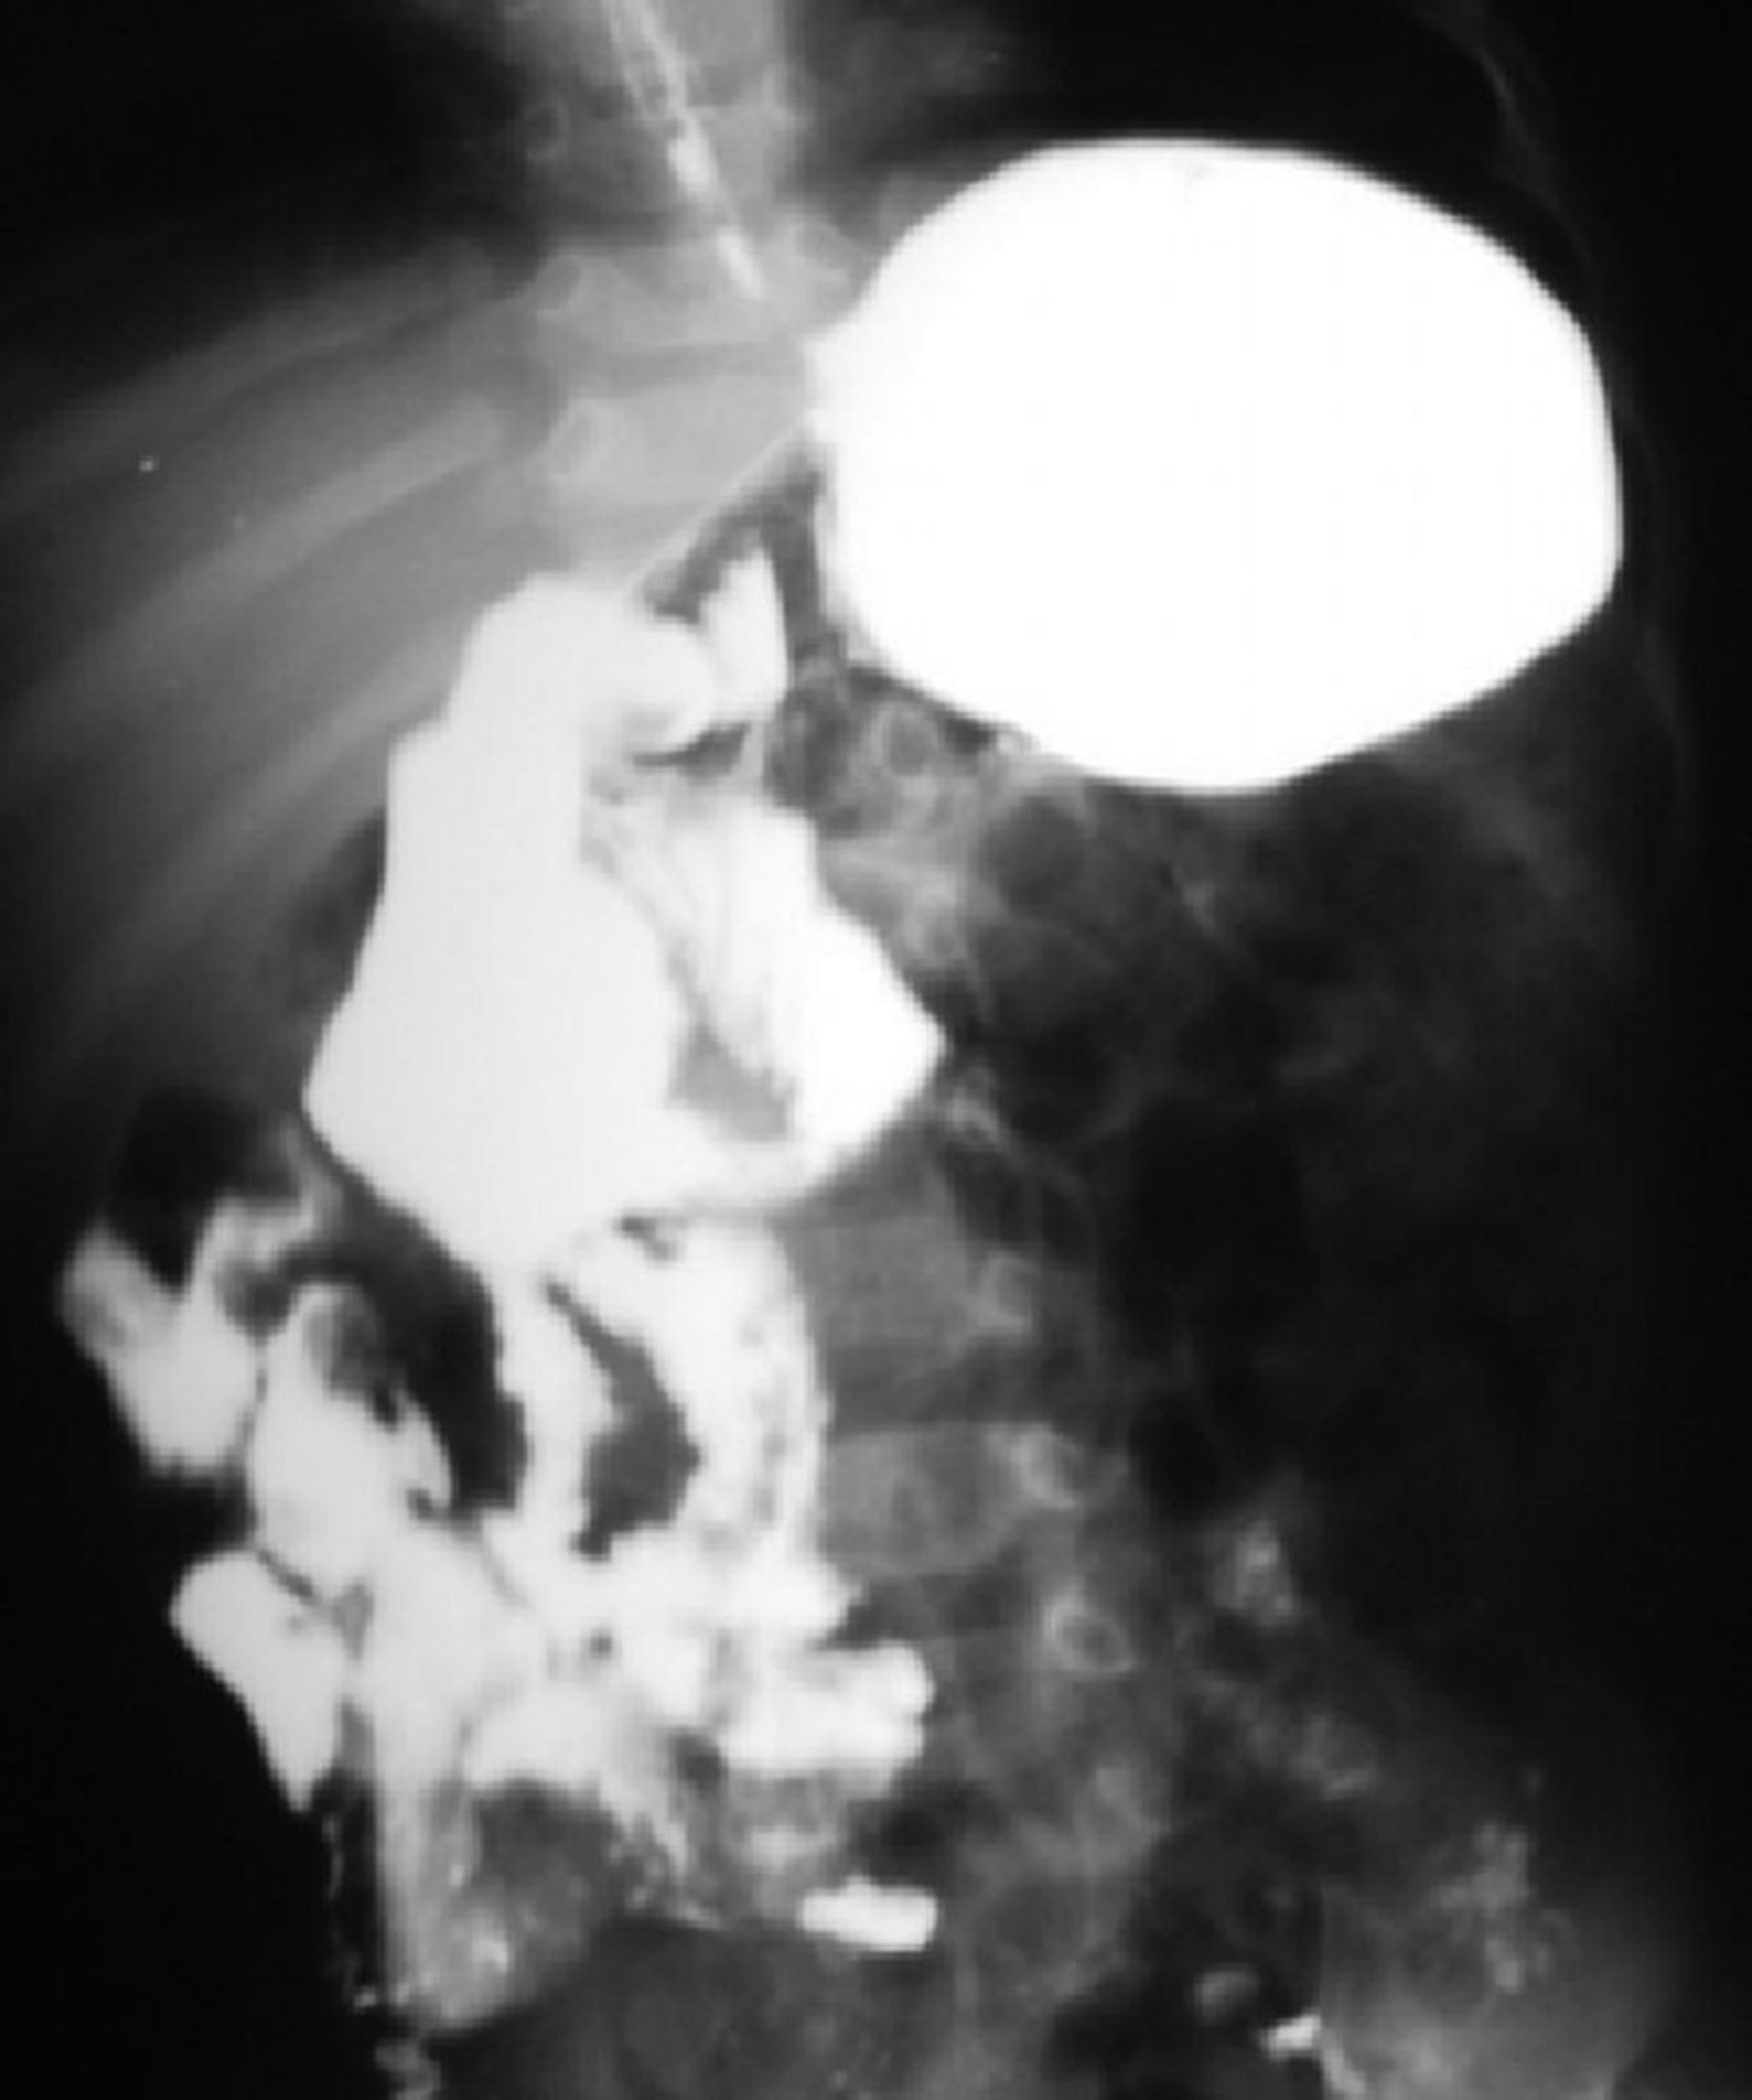

Malrotation of the Bowel

This barium study shows malrotation of the bowel. The duodenojejunal junction is on the right side of the spine, and most of the small intestine is on the right side.